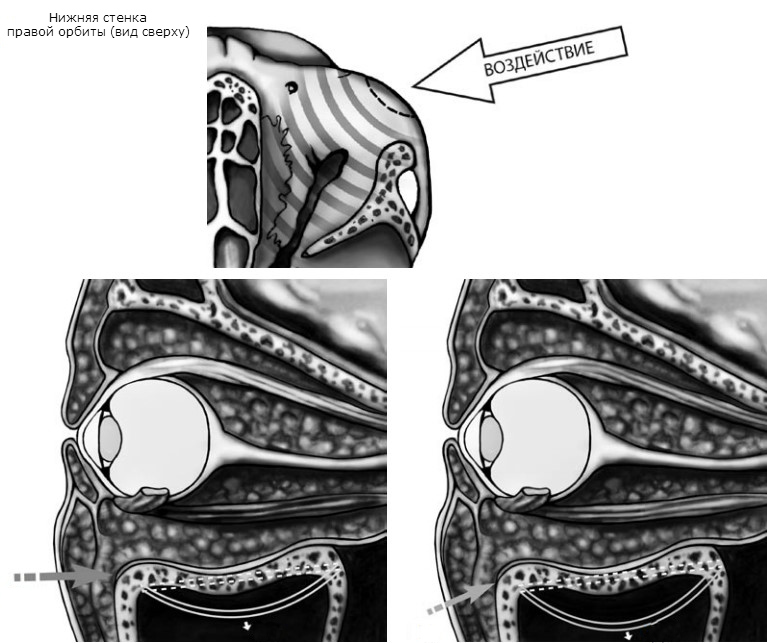

В зависимости от направления вектора силы дно орбиты (в первую очередь его внутренняя половина) испытывает или горизонтальную, или ротаторную деформацию. Площадь перелома будет максимальной в случае, если ранящий агент движется снизу-вверх под углом 30º к подглазничному краю. Кинетическая энергия, требующаяся для разрушения дна глазницы путем волнообразной деформации и через гидравлический удар, практически одинакова, но локализация и протяженность «гидравлических» и «механических» переломов существенно различаются. Экспериментальные исследования на кадаверных орбитах продемонстрировали, что переломы, обусловленные волнообразной деформацией, ограничиваются передней половиной внутренней части дна глазницы, не распространяются на медиальную стенку и не сопровождаются ущемлением мягких тканей в зоне костного дефекта.

Для изолированного «взрывного» перелома дна глазницы требуется меньше энергии, чем для повреждения медиальной стенки или возникновения инферо-медиального перелома. Этот, казалось бы, нелогичный, но давно известный клиницистам факт нашел свое объяснение в работе H. Takizawa с соавт. (1988). На основе экспериментов и последующего компьютерного моделирования авторы наглядно продемонстрировали, что очень важную роль играет не только толщина, но и контур (профиль) стенок глазницы. В частности, аркообразная крыша орбиты гораздо более устойчива к деформации, чем практически плоское дно, которое легче деформируется и ломается. Медиальная стенка еще более тонкая, но ее сзади наподобие контрфорсов укрепляют ячейки решетчатой кости. Поэтому для перелома медиальной стенки требуется больше механической энергии, чем для разрушения глазничного дна.

Способствуют повреждению дна орбиты такие анатомические образования, как нижняя глазничная щель, подглазничная борозда и канал, а также рефлекторное сокращение круговой мышцы глаза и наличие под орбитой большой воздухоносной полости. Именно недоразвитием верхнечелюстной пазухи и продолжающимся ростом глазницы объясняется редкость возникновения переломов дна орбиты у детей до 7–8 лет. Если фрактура все же возникает, то реже чем у взрослых требует хирургического лечения.